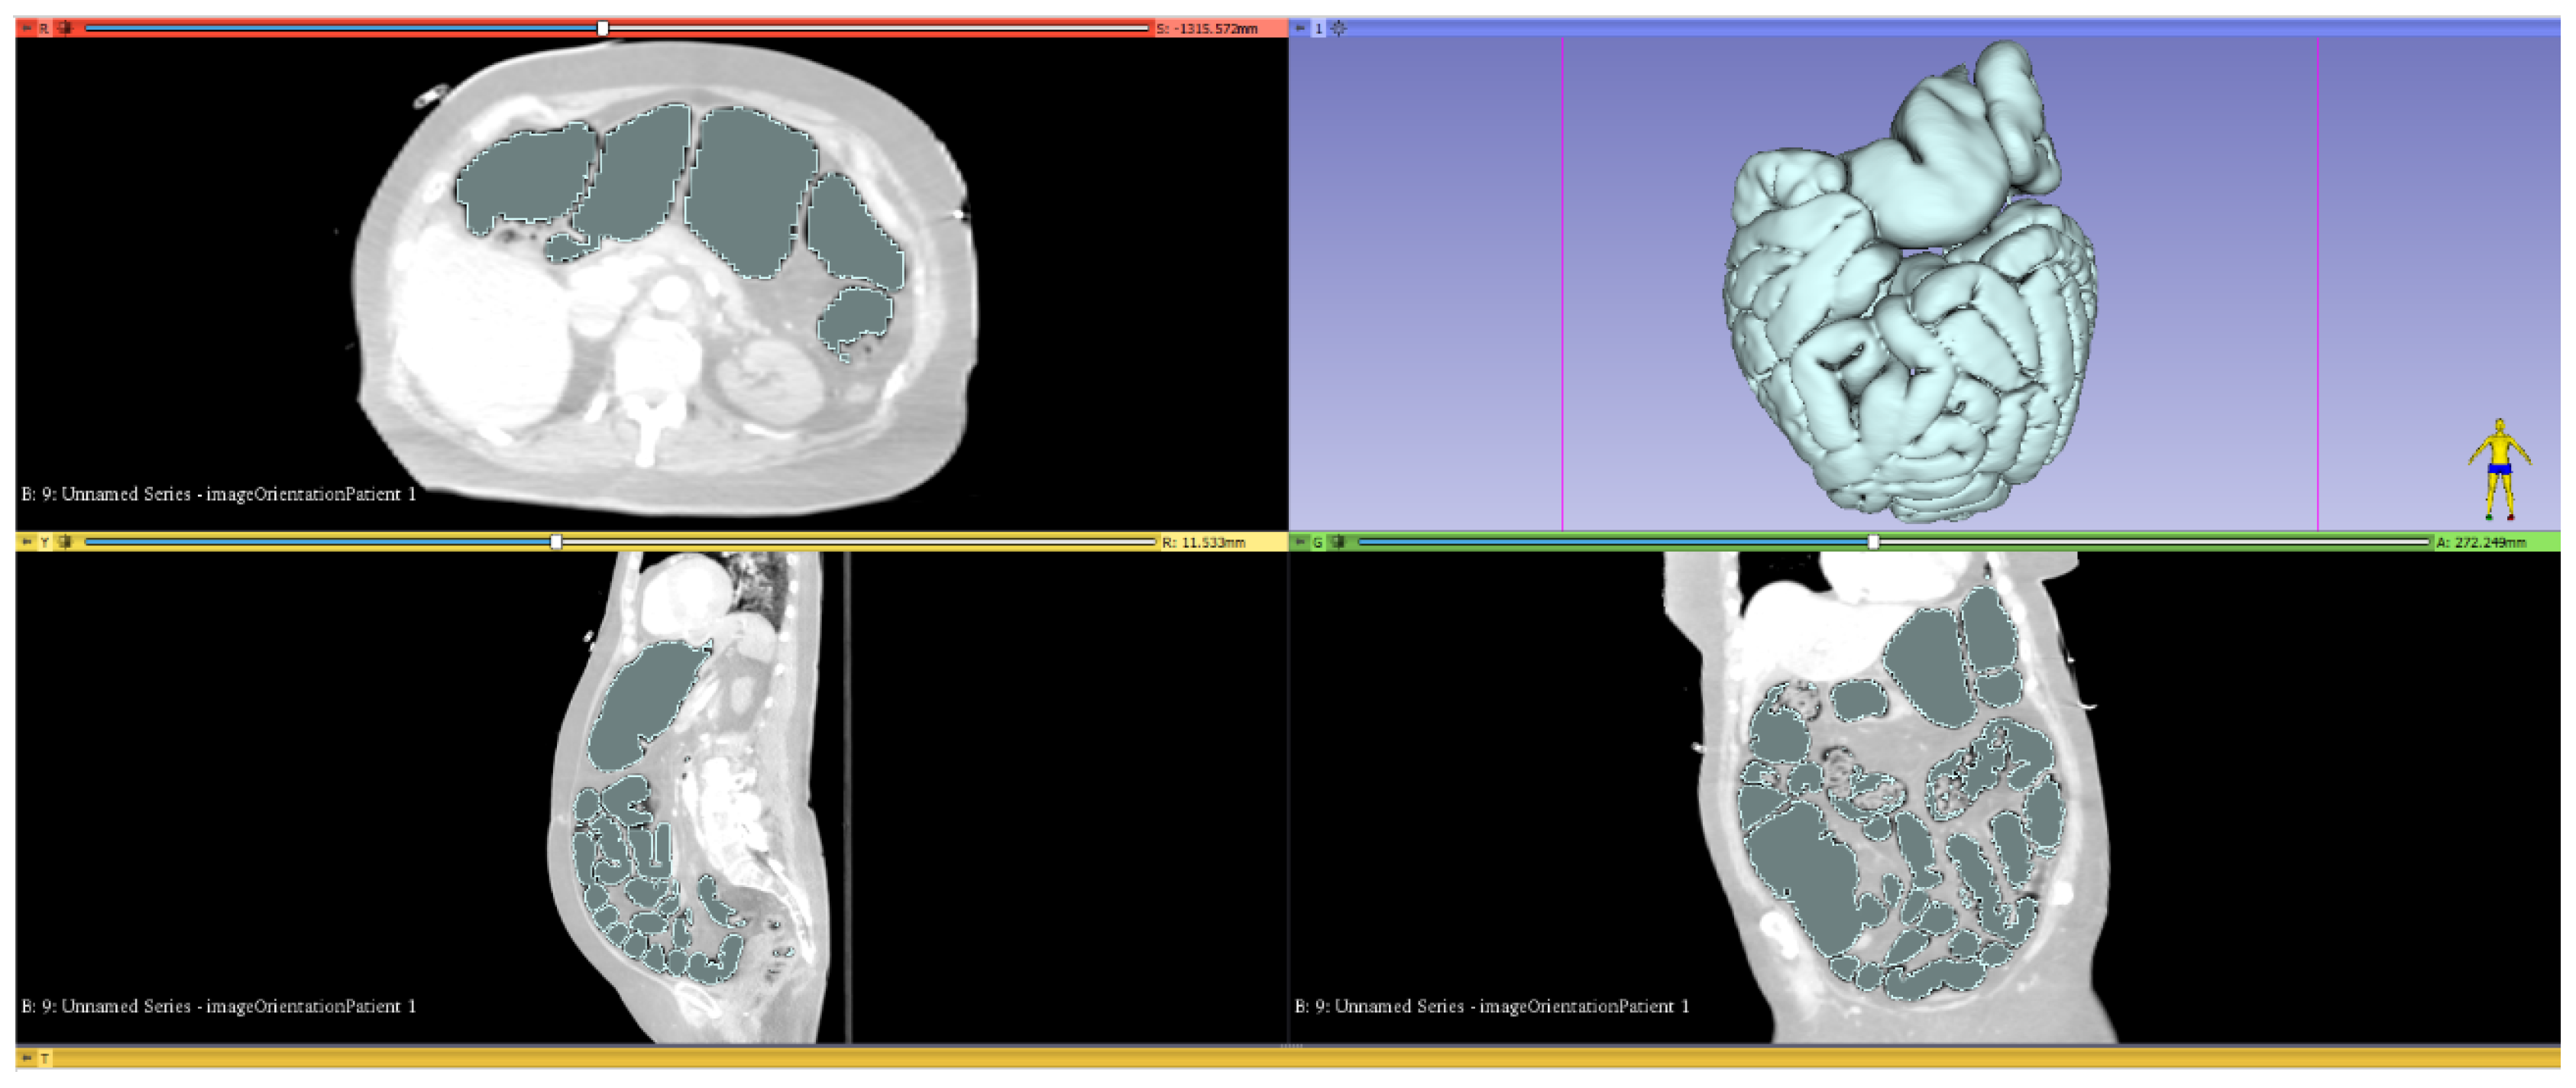

- The gas volume was determined using a threshold function. The measurement range was defined as −500 to −1024 HU. By definition, air has an HU value of −1000 HU. As the air is humidified and voxels are sometimes a mix of solids and gas in the MDT, the measuring range for the volumetry must be adjusted accordingly. If the measuring range is larger, a larger volume is calculated. After reviewing various studies on this topic, we ultimately decided in favor of a threshold range from −500 to −1024 HU [22,30,31]. Whether this optimally represents the actual volume is unclear. Furthermore, to the best of our knowledge, there is no method that includes the expected compression of the gas due to the intra-abdominal pressure increase in the calculation.